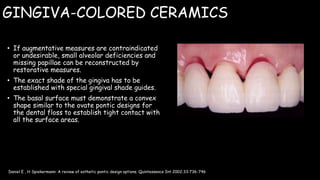

The document discusses pontic design for fixed dental prostheses. It covers pretreatment assessment of residual ridge contours, classifications of ridge deformities, surgical modification techniques, and ideal requirements for pontics. Pontic designs are classified based on their shape and materials. Factors in pontic selection include esthetics and oral hygiene. Common designs for anterior and posterior regions are described, including sanitary, ovate, and saddle pontics. Biological considerations for pontic design involve maintaining the residual ridge, abutment teeth, and supporting tissues.